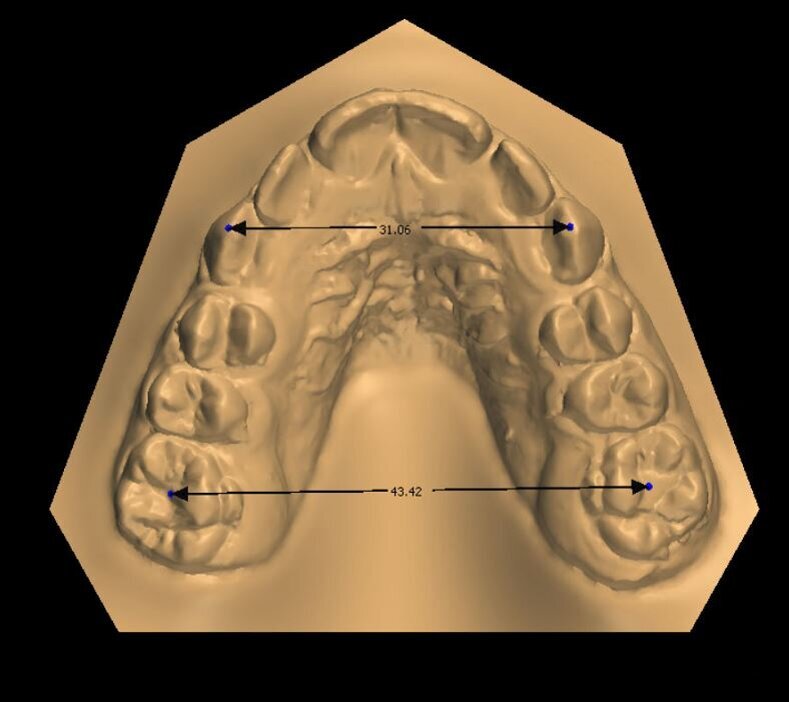

_Materiale e metodi Una paziente di sesso femminile di 11 anni, presenta all’esame clinico: dentizione permanente, palato di forma ogivale, discrepanza trasversale, affollamento e contrazione dell’arcata superiore, tipping vestibolare dei primi molari superiori, marcato affollamento dentale inferiore, tipping linguale degli elementi dentali postero-inferiori, proinclinazione vestibolare degli incisivi inferiori (Fig. 1). La paziente, inoltre, riferisce il menarca sei mesi prima dell’inizio della terapia. Per prima cosa è stato realizzato un setup digitale del risultato finale nell’arcata inferiore correggendo l’affollamento mediante espansione dei settori posteriori e minimizzando la proinclinazione degli incisivi. Utilizzando questo setup digitale come arcata guida, è risultata una discrepanza trasversale tra arcata inferiore e arcata superiore di circa 6 mm (Fig. 2).Richiesto l’esame CBCT, è stata valutata anche la morfologia della sutura palatina ed è risultata di tipo C secondo la classificazione di Angelieri et al11 (Fig. 3).

Fig. 6a_Misurazione distanza inter-molare e inter-canina a inizio terapia.